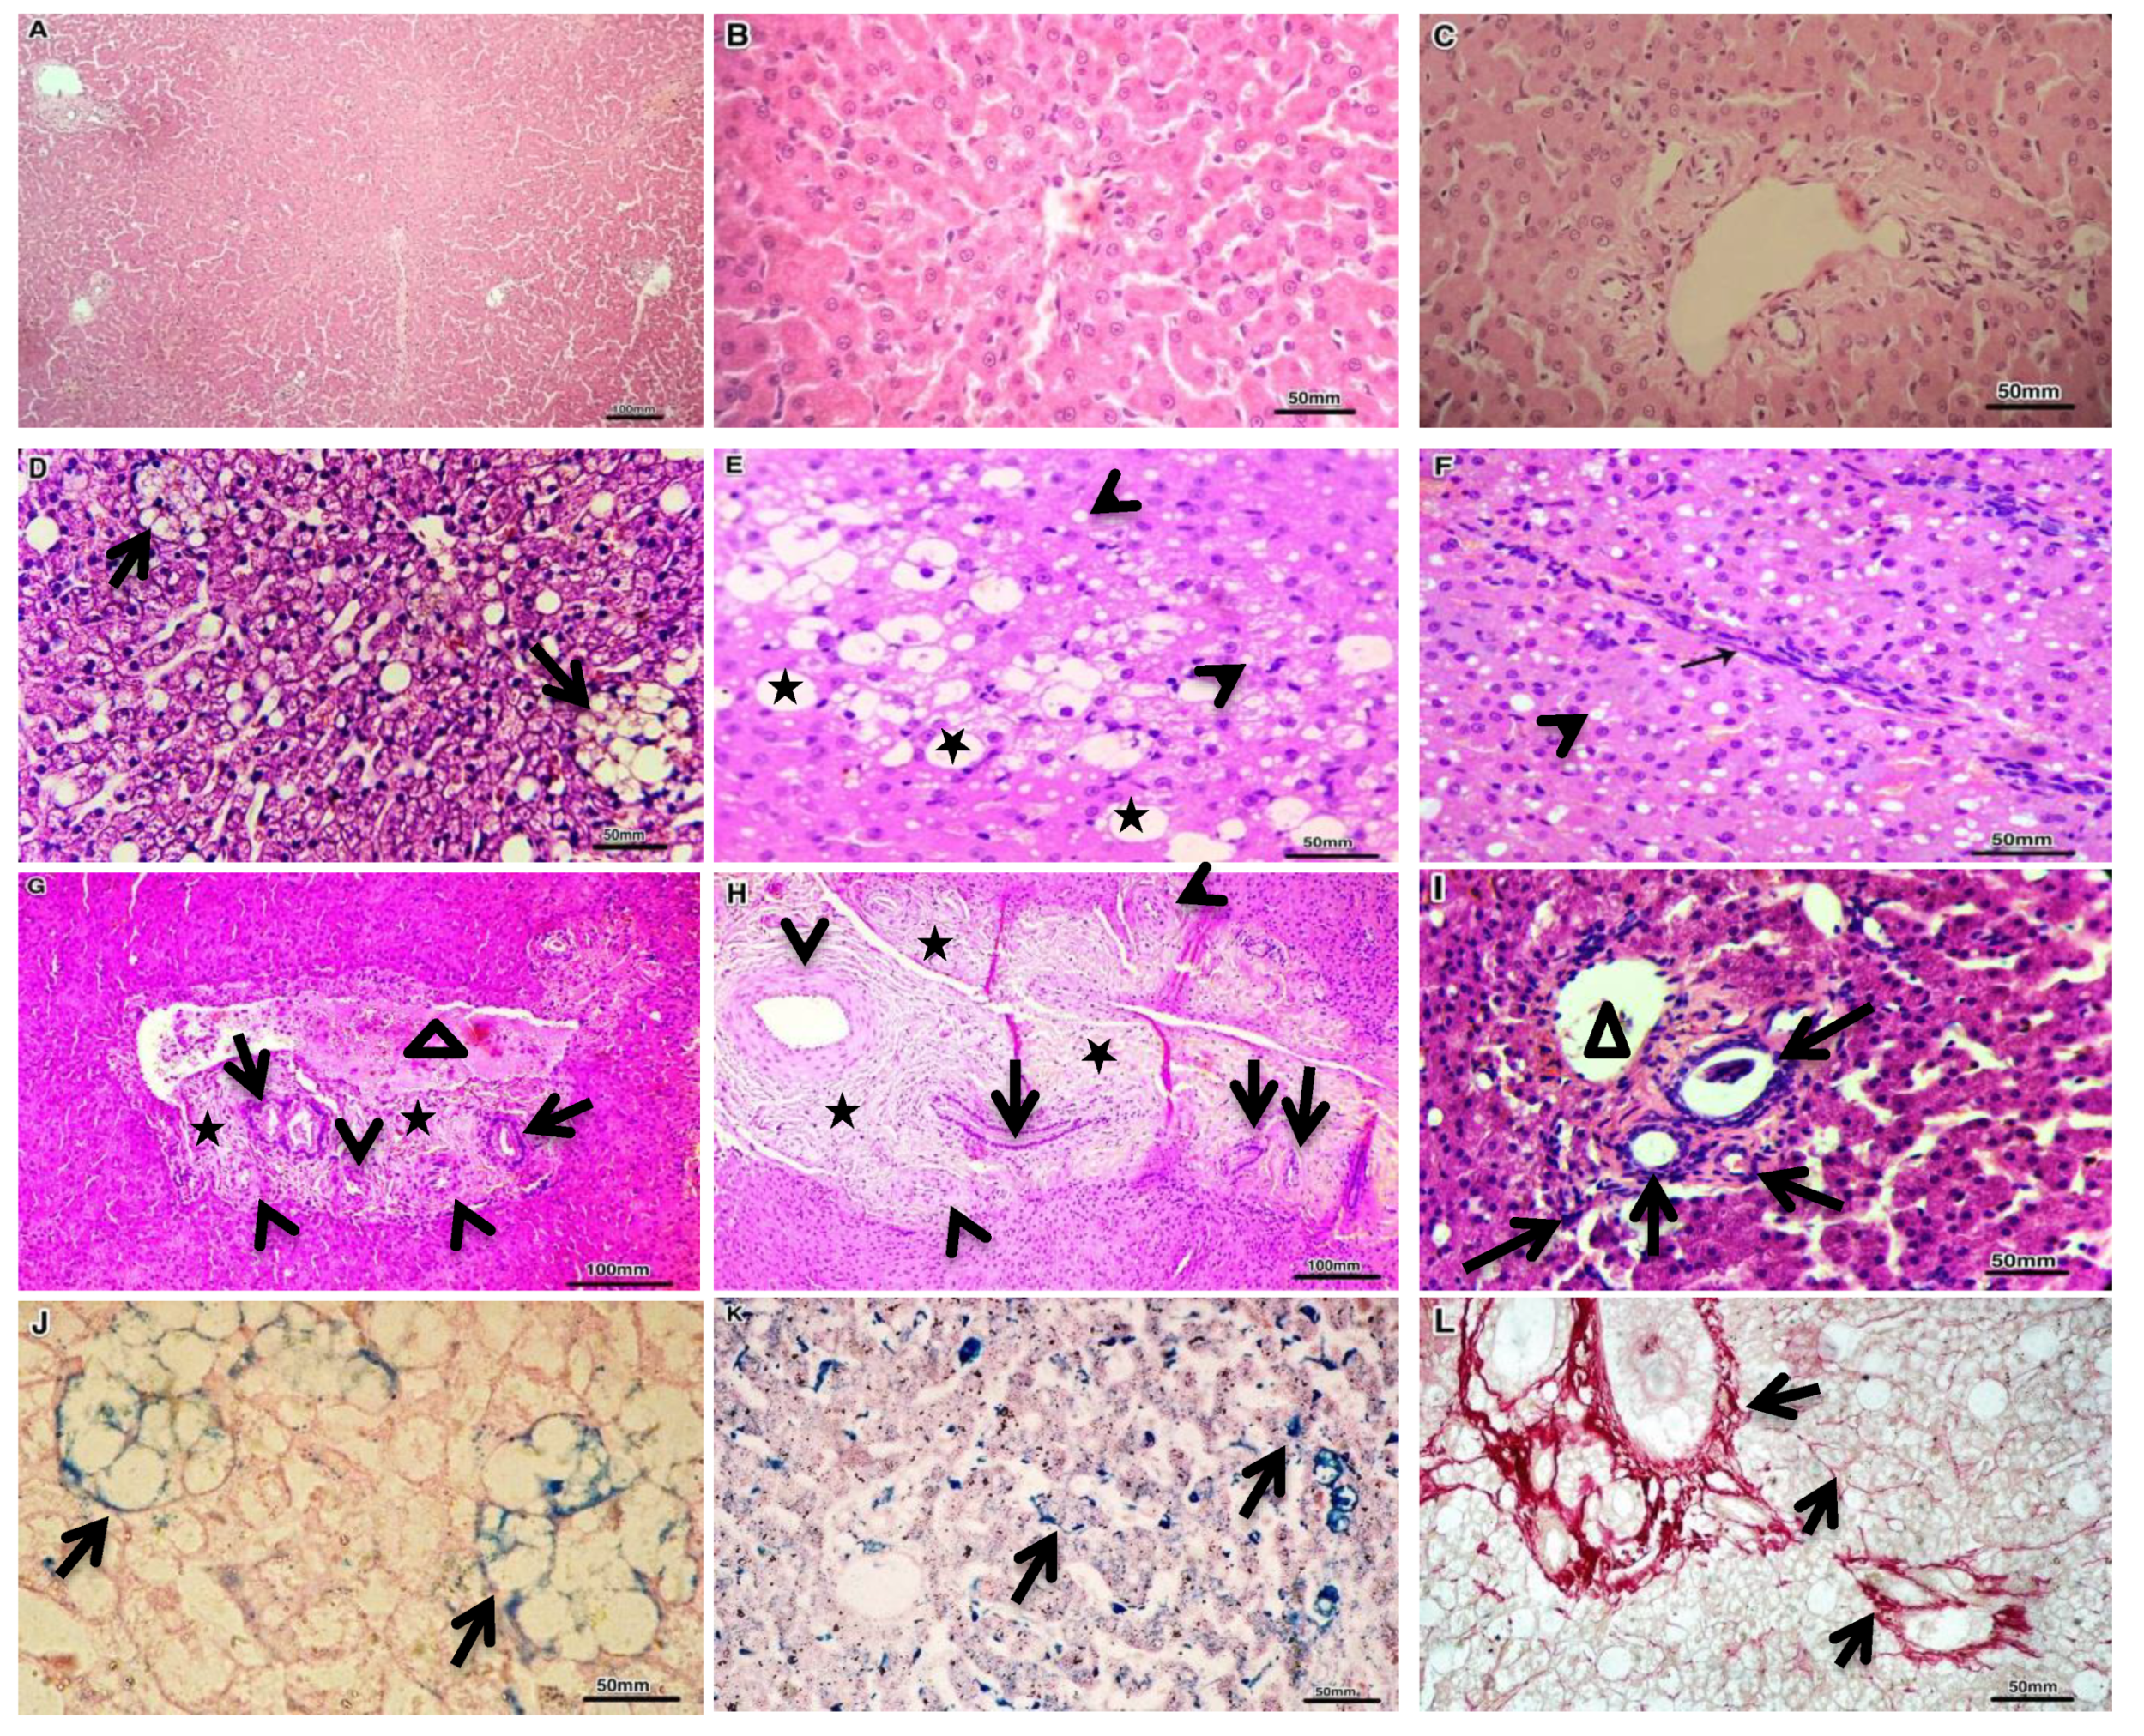

3.4. Expression Profile of the Studied Cfa-Mirnas in the Investigated Groups Compared to the Control Group